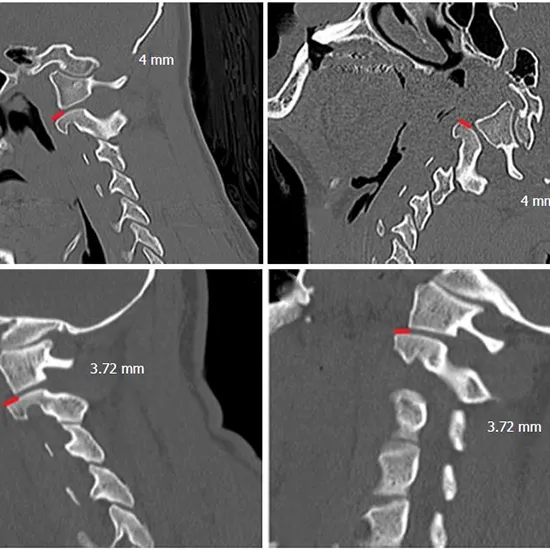

The craniovertebral junction (CVJ) is visible in most magnetic resonance (MR) imaging studies of the brain and consists of the occiput, atlas, and axis.

Magnetic Resonance Imaging CV (Craniovertebral) Junction images the back of the head, foramen magnum, and the first two cervical vertebrae.